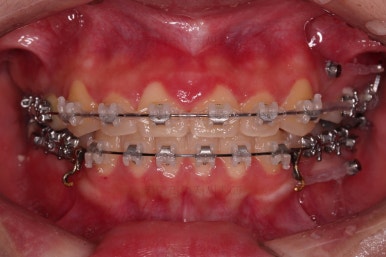

틈새는 거의 다 붙어가는데 교합이나 중앙선 등을 위해 추가적으로 밀고 당기기를 해줍니다.

디테일을 좀 더 맞추고 부산치아교정 마무리를 합니다.

치아 갯수 및 사이즈 문제로 위아래의 정중선은 100% 일치시키긴 힘들지만 가능한 선에서 최대한 맞추었고요.

윗니가 1개 없는 상태에서의 교합도 잘 맞추고 마무리를 했습니다.

다시 틈새가 벌어지지 말라고 유지철사를 붙여주었고요.